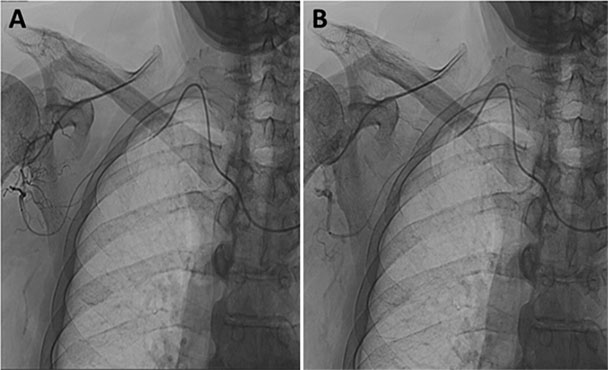

Schultergelenk